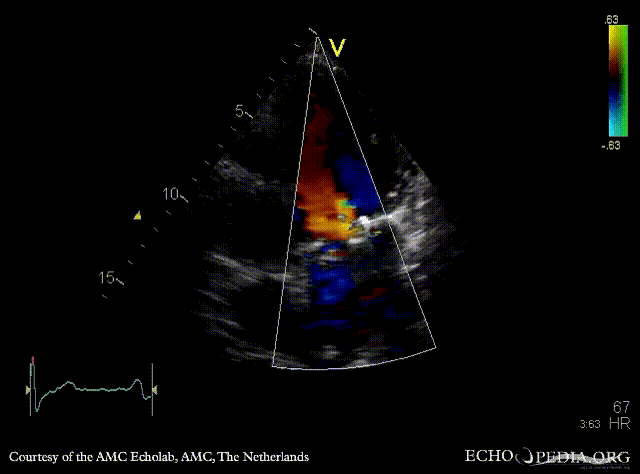

Mechanical mitral valve prosthesis

Courtesy of: AMC Echolab, AMC, The Netherlands

PLAX: mechanical mitral valve prosthesis, dilated left ventricle and left atrium PLAX with Color Dopler: no mitral regurgitation